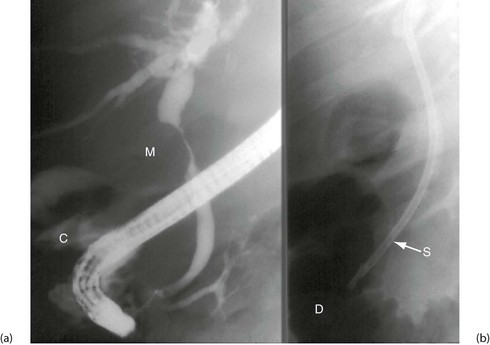

Fig. 5.6 Some techniques for demonstrating the biliary system

(a) and (b) Endoscopic retrograde cholangiography

The patient is sedated and a side-viewing gastroscope passed down so the tip reaches the second part of the duodenum. The ampulla of Vater is cannulated under direct vision and contrast medium injected to outline the bile ducts. (b) A large gallstone C is seen within the dilated common bile duct and a collection of radiopaque gallstones GS is seen in the gall bladder

Endoscopic retrograde cholangio-pancreatography (ERCP): This is described below (see Diagnostic and therapeutic duodenoscopy); its use in obstructive jaundice is described in detail in Chapter 18. The basic technique is illustrated in Figure 5.6 a and b.